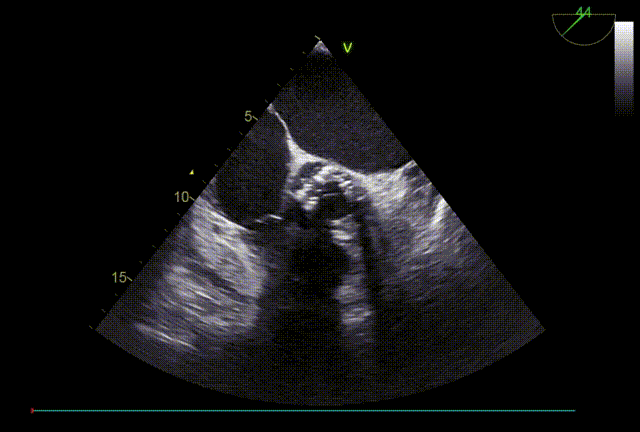

TTE